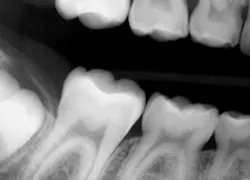

Digital sensors have many advantages over traditional X-ray film. One of the downsides is the lack of flexibility, which often results in an incorrectly positioned exposure, such as this example of a bitewing (Fig 1). If this is a challenge for you or you are looking for a time saving way to take X-rays, check out Flaps. Made of soft polyethylene, latex-free foam, they come in two sizes, original and long. Flaps can be used for horizontal or vertical bitewings and any periapical exposure. They accommodate all sizes of film and sensors — #0, #1, and #2.